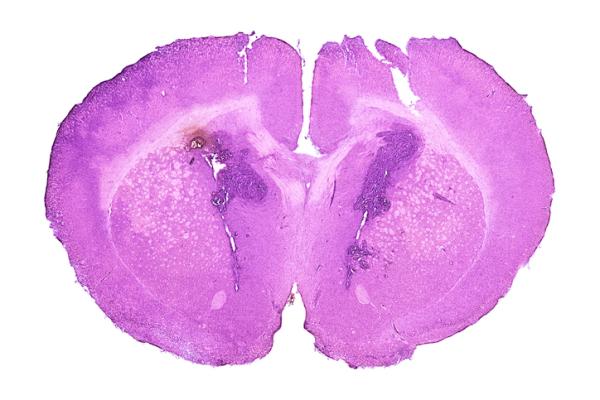

Gliomas are the most common type of primary malignant brain tumors in adults, accounting for nearly 8 in 10 of these tumors. In 2021, the World Health Organization (WHO) reclassified gliomas to reflect the discovery of new biomarkers, including mutations to the genes that encode isocitrate dehydrogenase (IDH) enzymes. IDH mutations occur in 70-80% of patients with lower-grade diffuse gliomas, and patients with IDH mutations tend to have longer survival than patients without them.

Recommendations in the guideline address the indications and optimal timing, as well as planning and delivery techniques, for radiation therapy in adult patients with IDH-mutant, WHO grade 2 and grade 3 glioma, including oligodendroglioma and astrocytoma. The guideline also addresses clinical management of adverse effects and includes an algorithm that summarizes the treatment paths. Key recommendations are as follows: